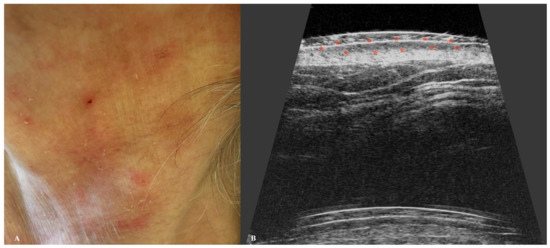

5. Melanoma

| Melanoma | Hypoechoic, heterogeneous lesion with an oblong or oval shape. Often well demarcated by a hyperechoic epidermal layer. Hypervascular on Doppler. |